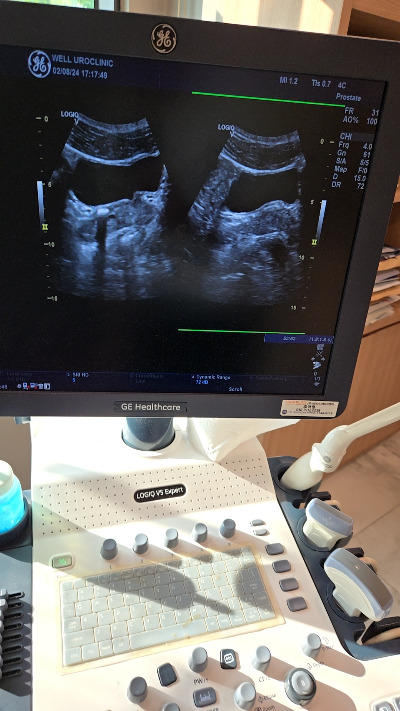

당연히 내가 운동을 강박증처럼 조금 무리하면서 했다고 해서 이렇게 생긴 것도 맞지만 스트레스도 큰 원인이 있다고 말씀하셨다. 진료가 끝나고 병원에서 2군데 병원을 진료의뢰서를 써주셔서 비뇨기과+심장내과까지 가야 하는데 시간이 없어 비뇨기과 만 들려서 체외 충격파 쇄석술 결석 제거 수술을 받았는데 너무 아팠고 통풍만큼의 고통이었다.

img.jpg 1.5cm결석,조금만한 결석들 체외충격파 쇄석술 드럽게 아프다...